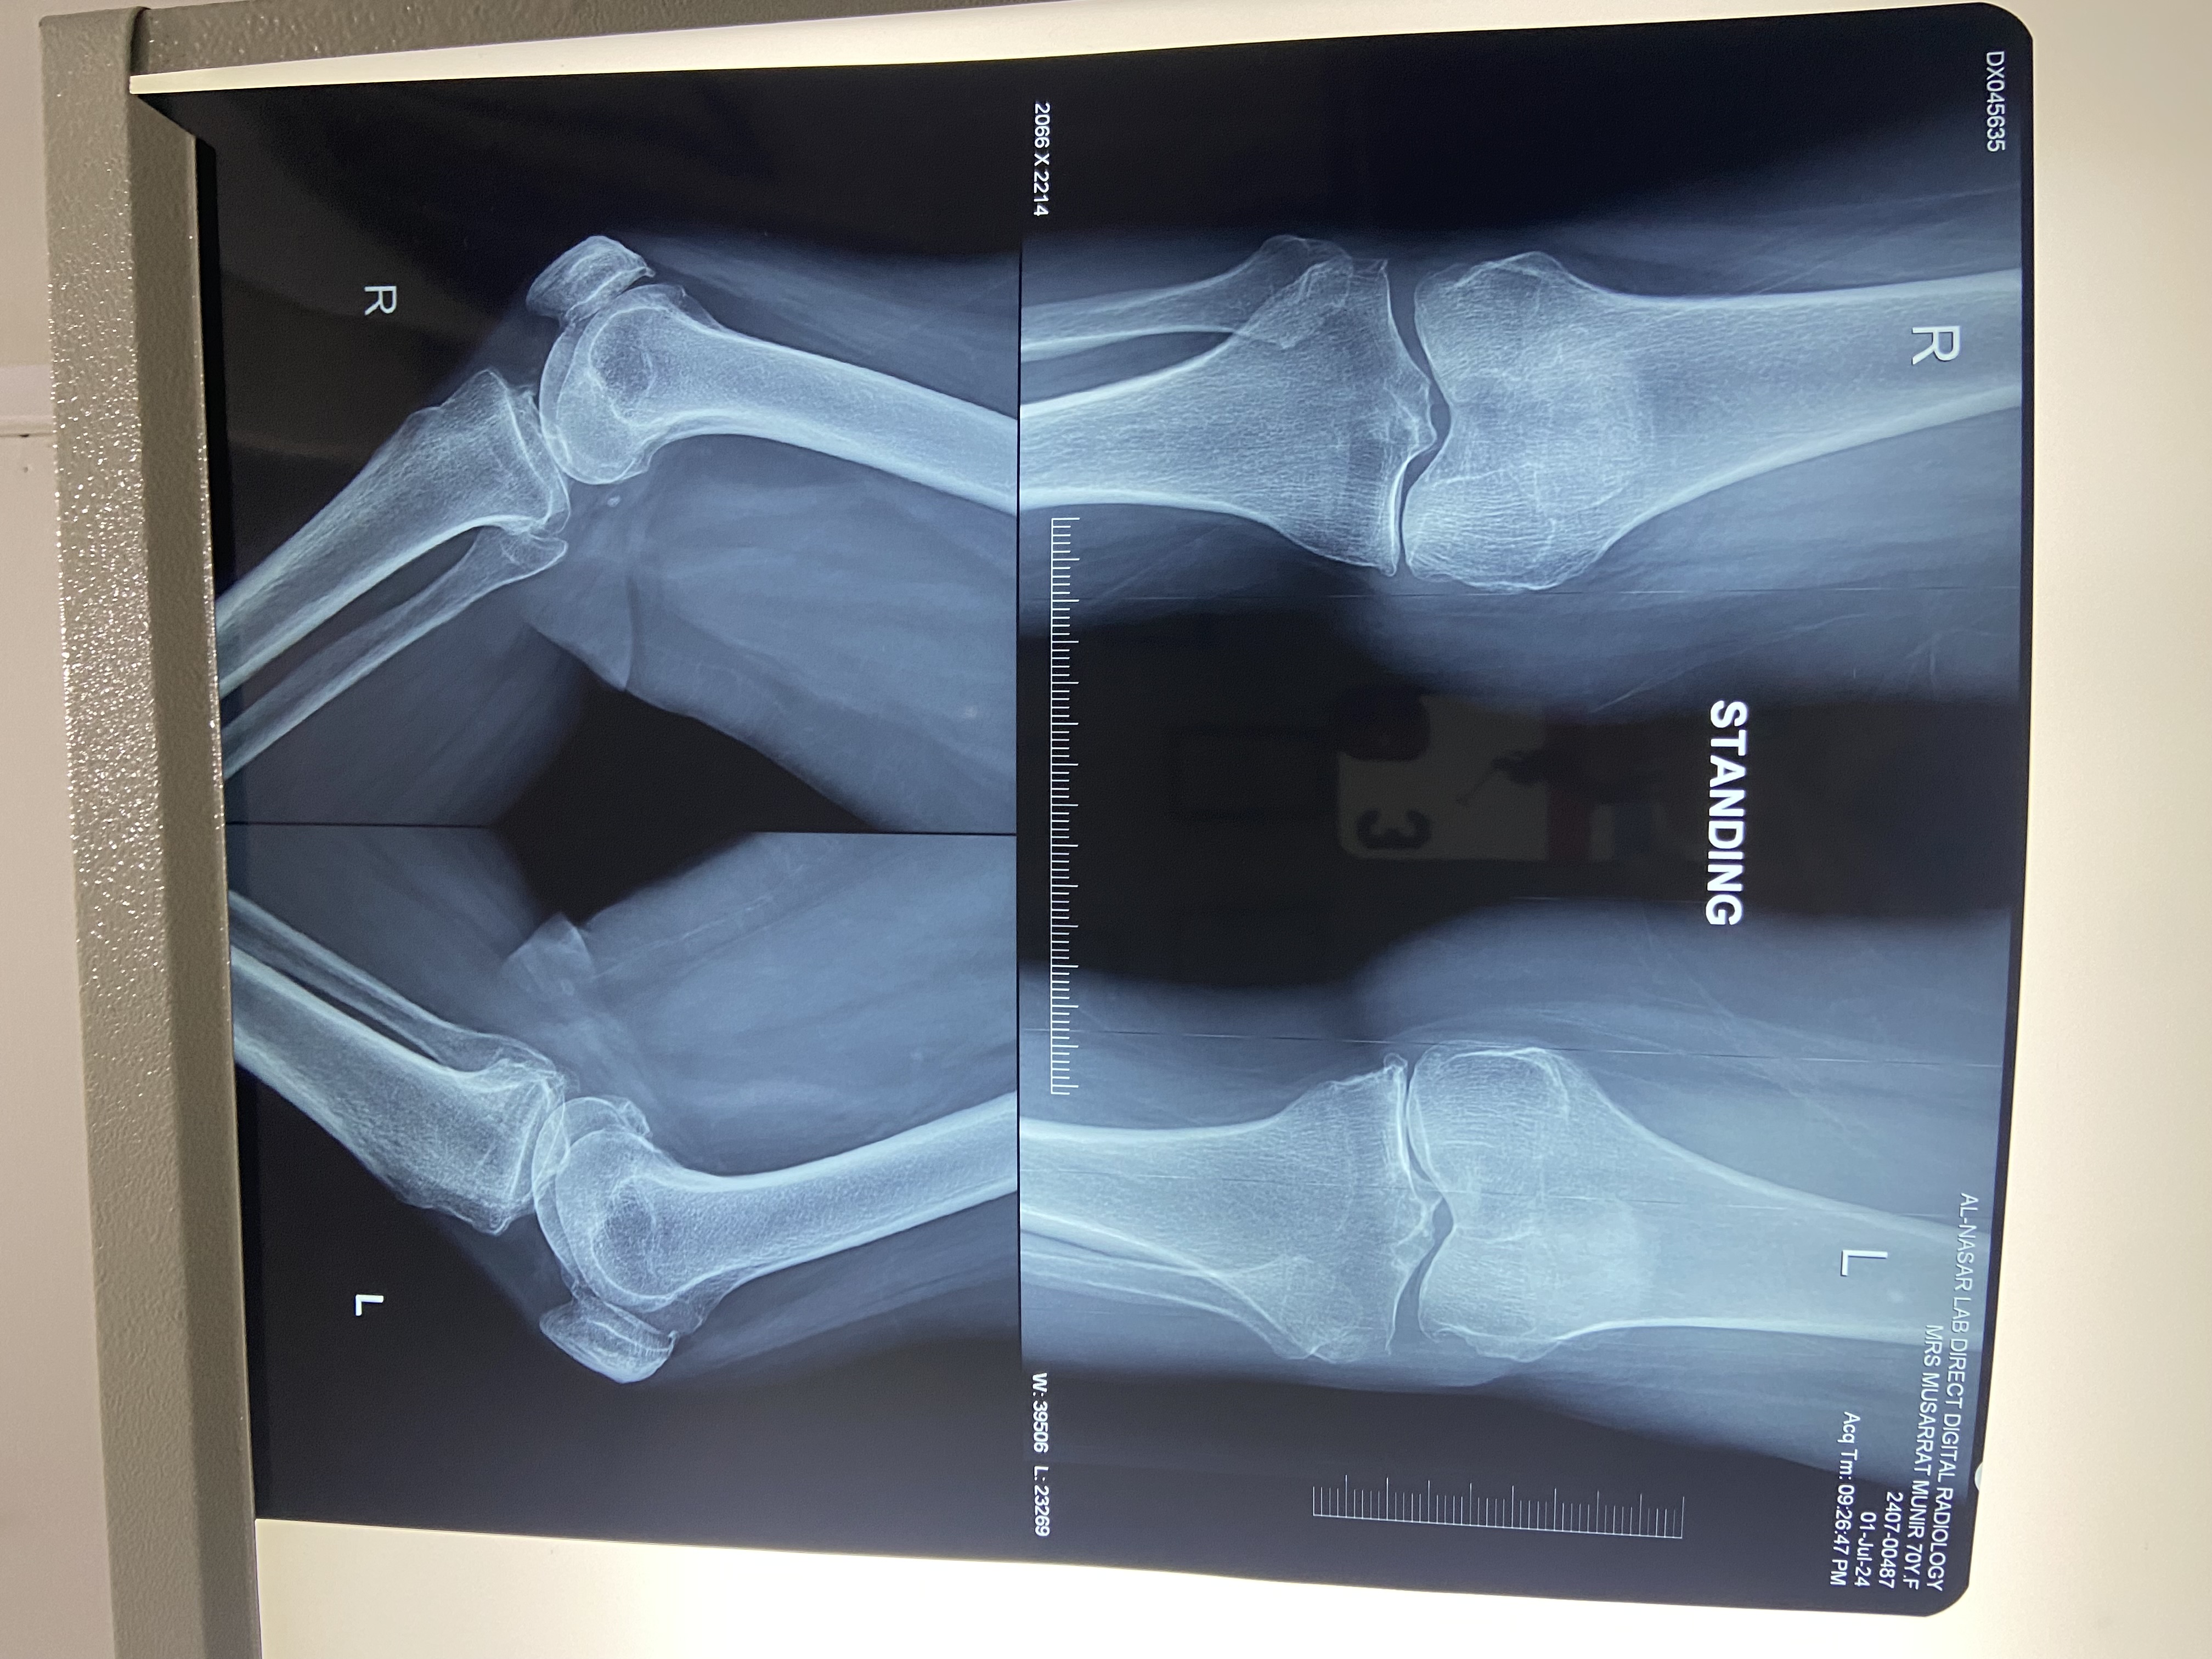

Plz get tests done as

CBC+ESR

URINE C/E

S/Ca

S/Vit D3

X-ray both knees AP view, standing

There has to be some kind of inflammation in your knees if there is no history of injury.

You should get your Serum URIC Acid, RAFactor, ESR and ASO Titre + X Rays of your knees done.

Diagnosis is must before starting any kind of treatment blindly.